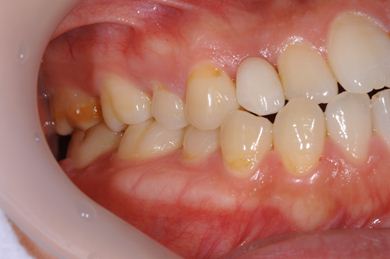

治療後

• 治療後